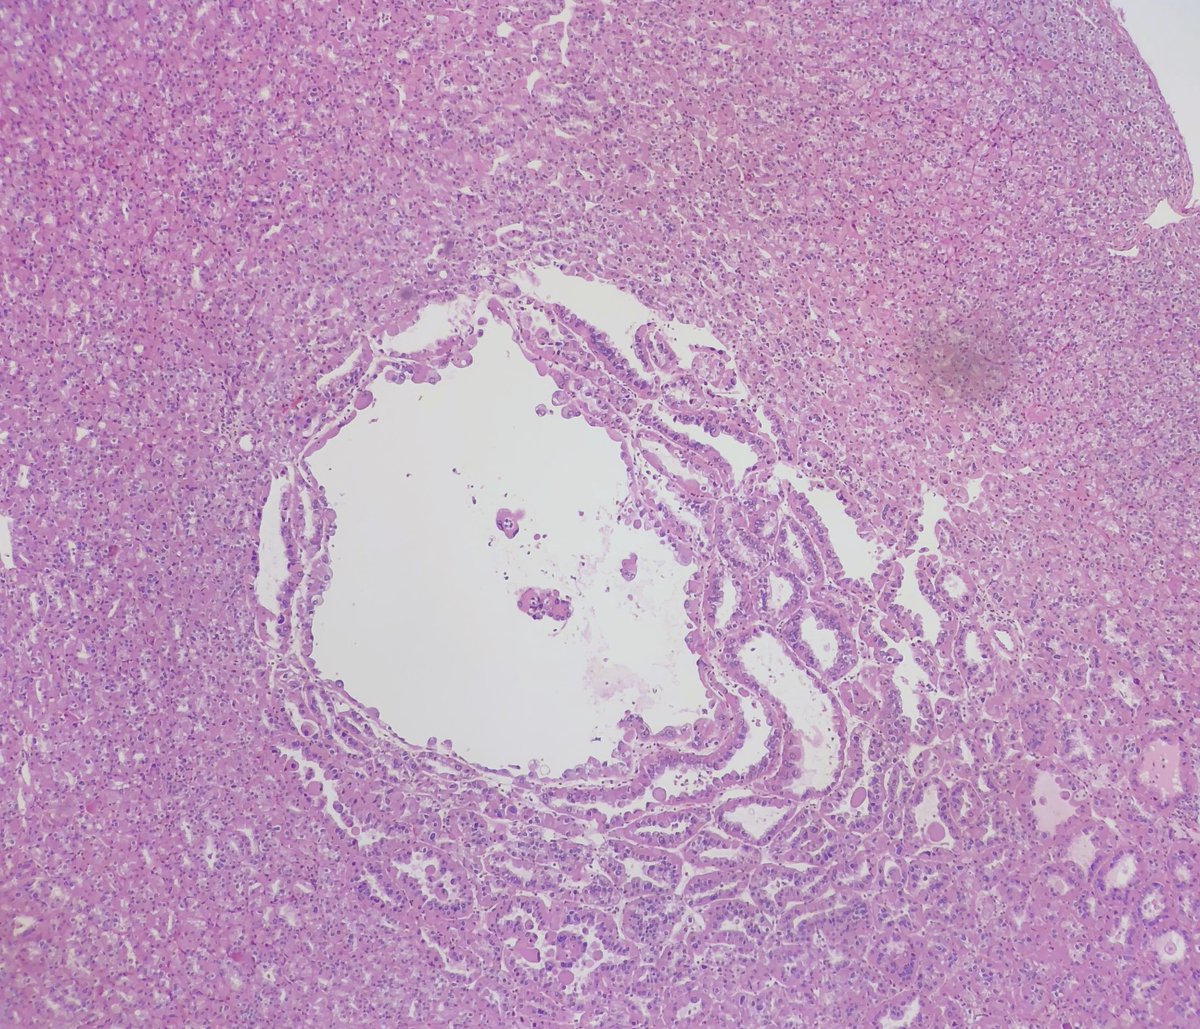

30 YO woman returning from Zambia with hematuria. Cystoscopy shows a bladder “nodule”.

Acute and chronic cystitis with abundant eosinophils. Ova and helminths are seen.